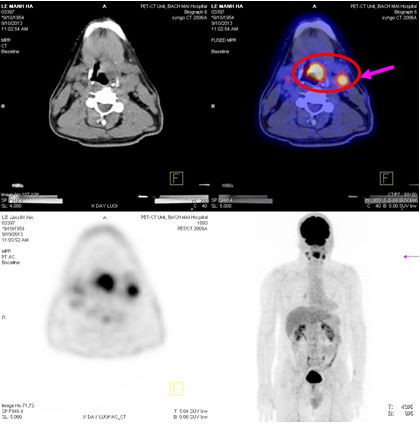

Trên hình ảnh PET/CT:

- Vùng đáy lưỡi có khối lớn kéo dài đến thanh quản kích thước: 2,4x3,6x2,9cm, tăng hấp thu F18- FDG max SUV=8,28.

- Hạch góc hàm trái kích thước: 1,9cm, tăng hấp thu F18- FDG max SUV=6,89. Hạch góc hàm phải kích thước: 1,8cm, max SUV=5,28. Hạch cảnh giữa phải kích thước: 1,3cm, max SUV=4,42.

Hình 3. Hình ảnh khối u vùng đáy lưỡi di căn hạch cổ hai bên trên hình ảnh PET/CT